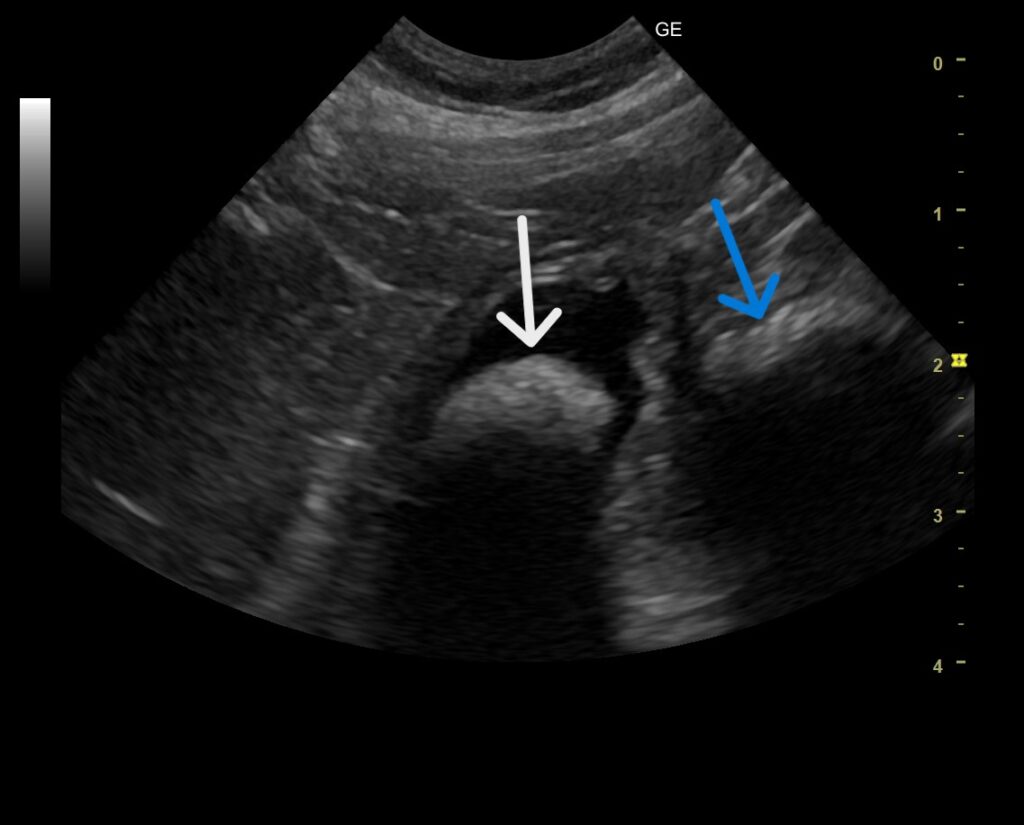

来院時のレントゲン検査ではひも状異物に特有なつづれ陰影などは認められませんでしたが、超音波検査で胃の出口にシャドーを引く丸い異物陰影と十二指腸へ続く線状の異物陰影を認めました。

幸いなことに、この時点で超音波検査でも腸の綴れはありませんでしたが、飼い主様には内視鏡で腸に流れた紐を摘出できなければ開腹手術になることをお伝えしてお預かりしました。

胃の中を内視鏡で見てみると、胃の出口に丸い異物がありました!

問診では丸い異物の情報はなかったのでひも状異物がクシャっと丸まっているのかなと想像していましたが、エコー検査で見た通りのしっかりと丸い異物が見つかりました。

おそらく丸い異物から紐が出ていて腸のほうに伸びているので丸い異物をつかんで慎重に引っ張てみます。